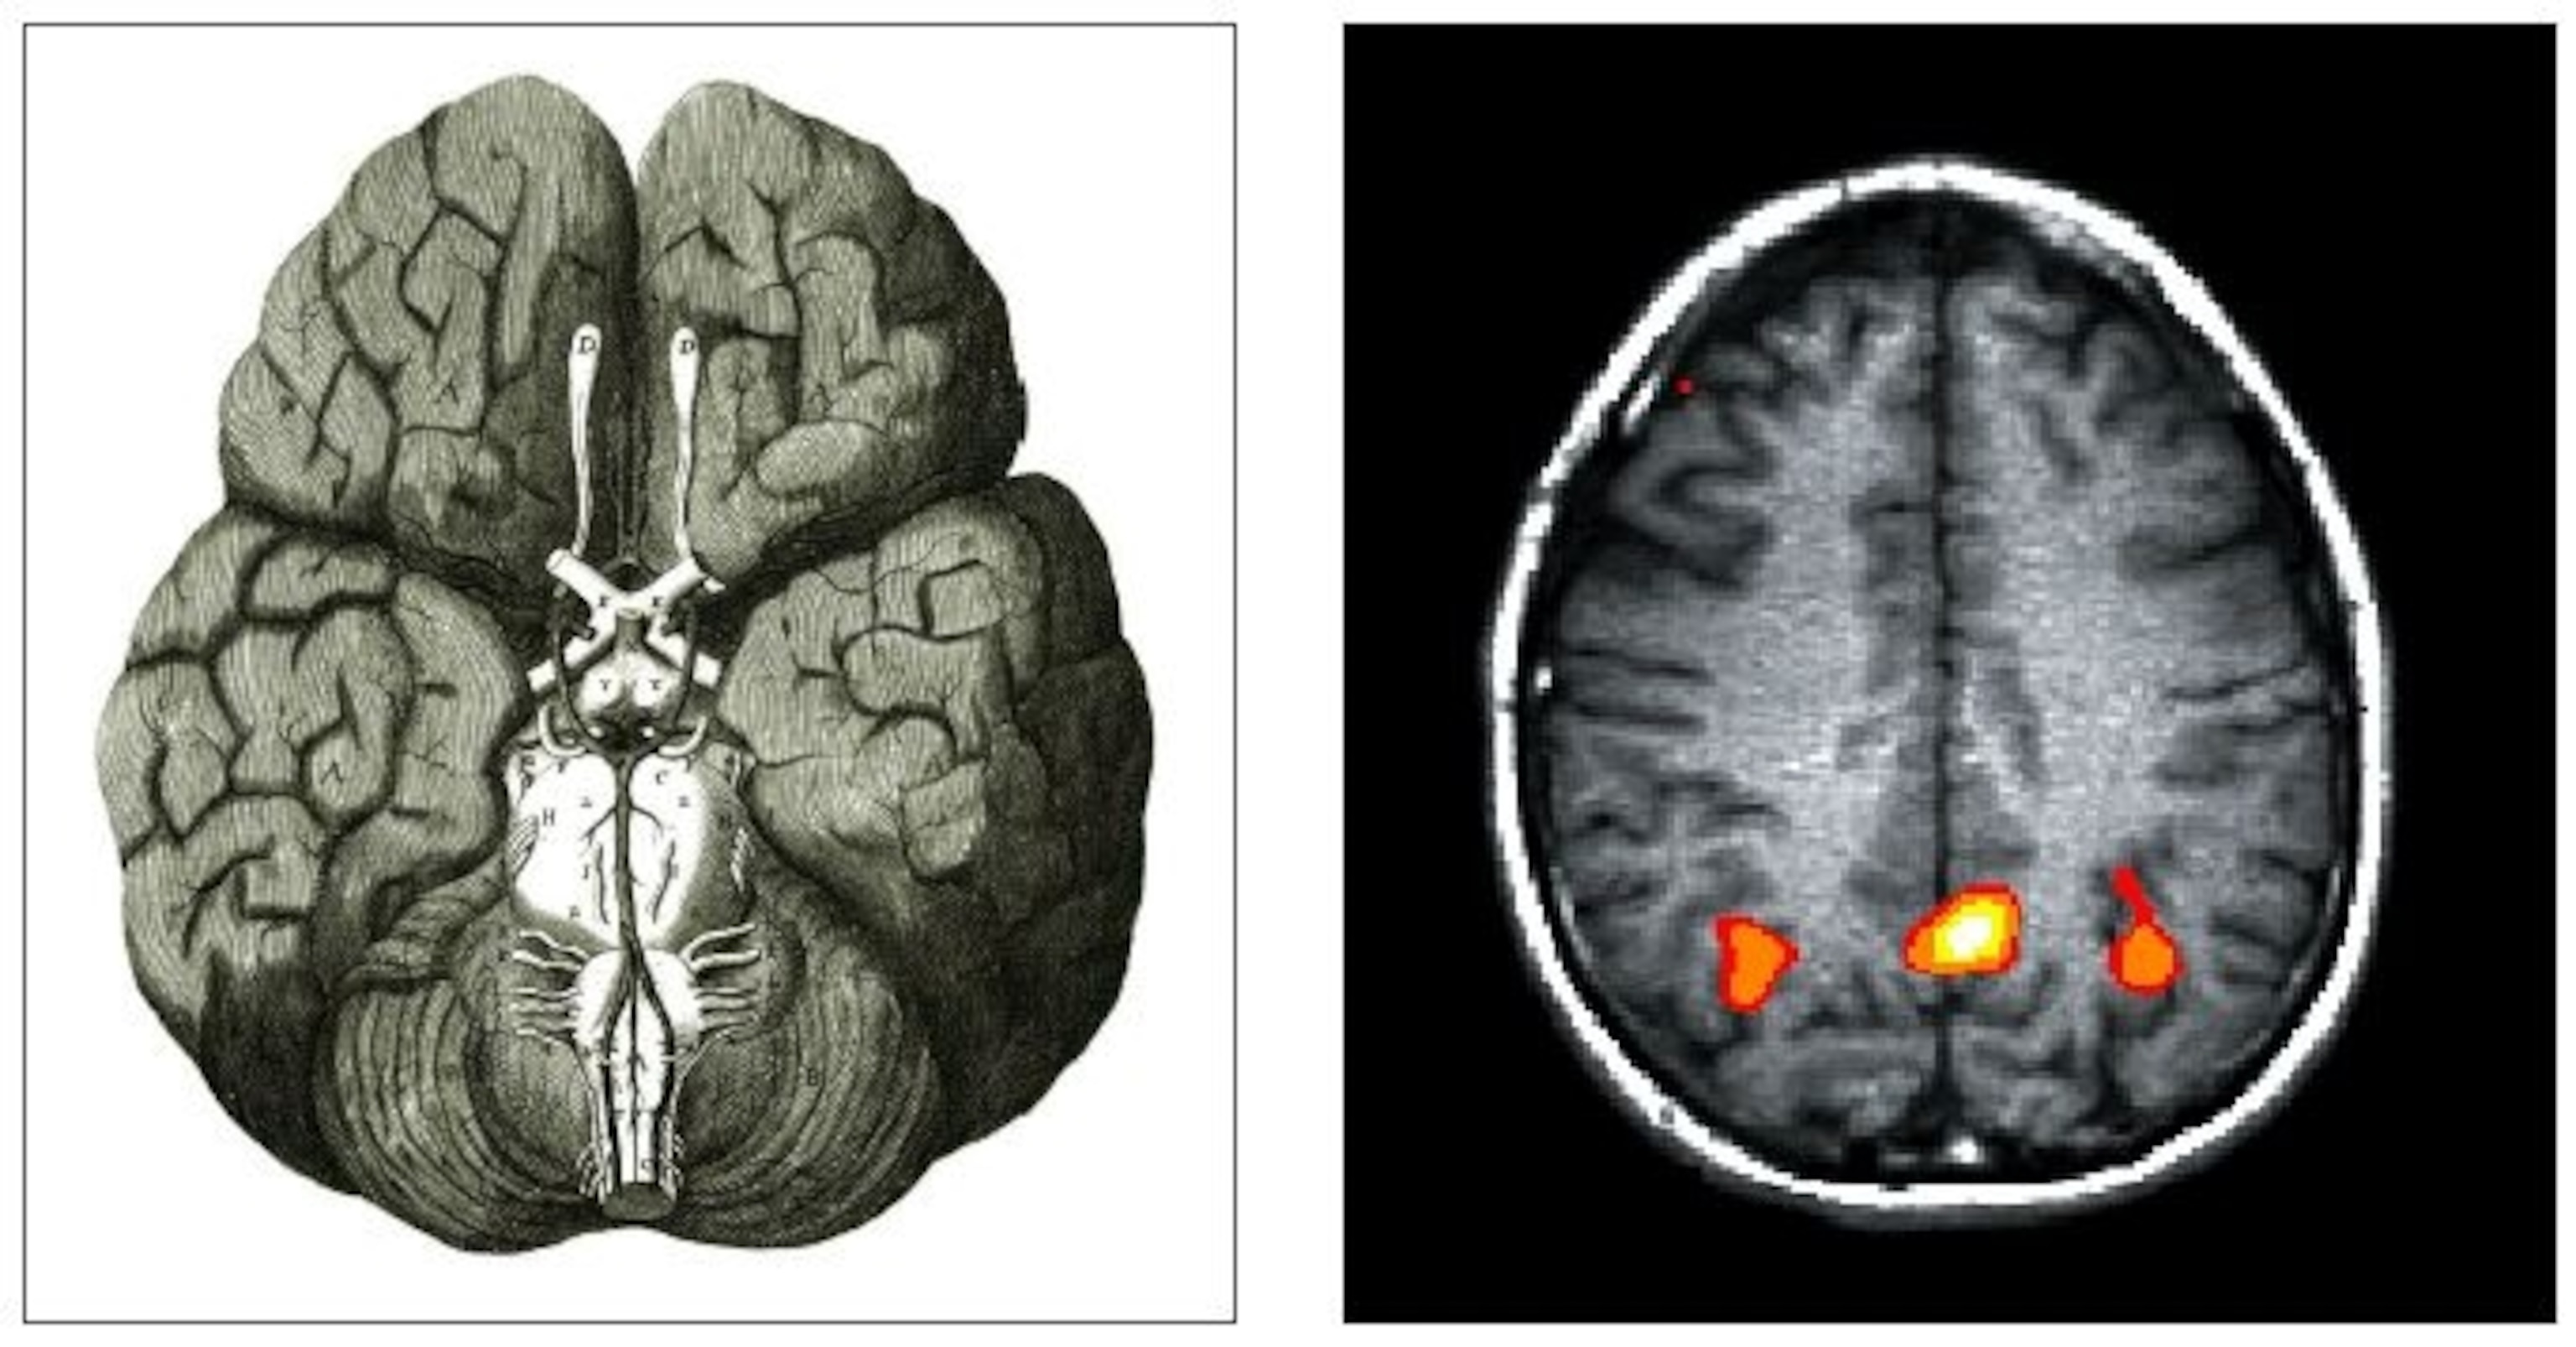

This philosophy had one particularly troubling aspect: how did the human mind fit into the world? Was it also just matter in motion? Thomas Hobbes was happy to say it was. Others didn’t want to be mistaken for atheists.Boyle’s friend Thomas Willis used the priniciples of the scientific revolution to get the first good understanding of the brain, which he envisioned as a chemical engine of memory, perception, and emotions.

Today this approach to nature has given rise to, among other things, brain-machine interfaces. If, as promised, they someday give paralyzed people some measure of control, they will be yet another example of promoting health through the mastery of nature. But the remarkable thing is what is being mastered here. As one of the bioengineers I spoke to pointed out, he and his colleagues don’t see the brain as some mysterious organ, but as a very complicated digital device that is sending out a series of 1s and 0s. By reading the code, they can do something with it. The brain itself–complete with its intentions and plans–has become yet another natural thing to be harnessed. In my opinion, this is both thrilling and terrifying.